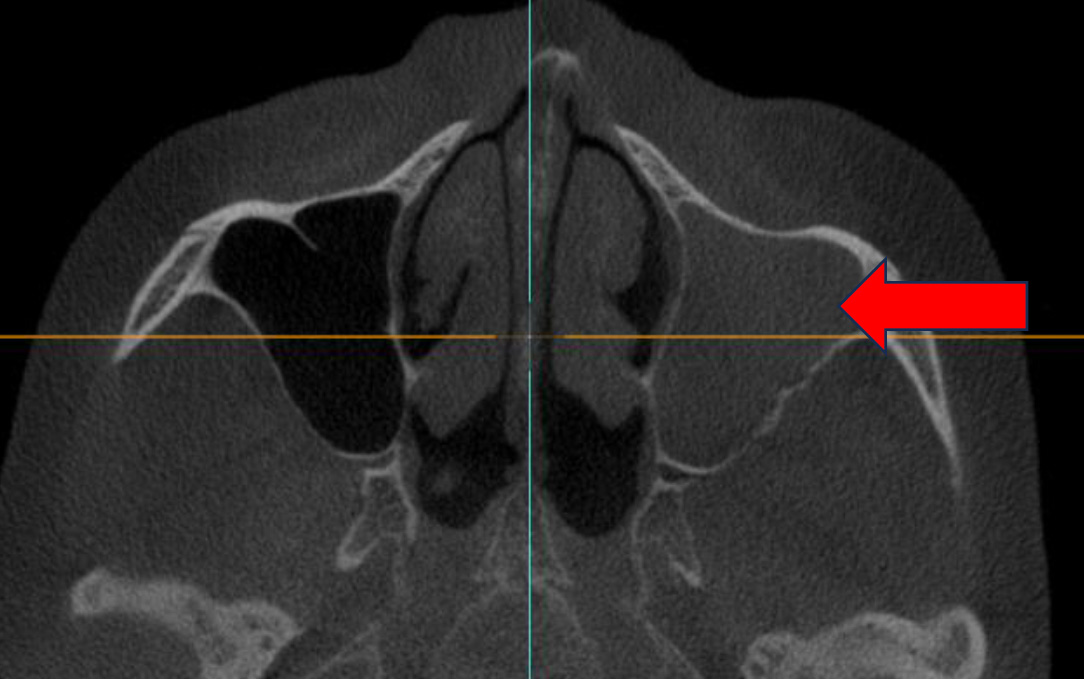

RESUME

CBCT October 2023